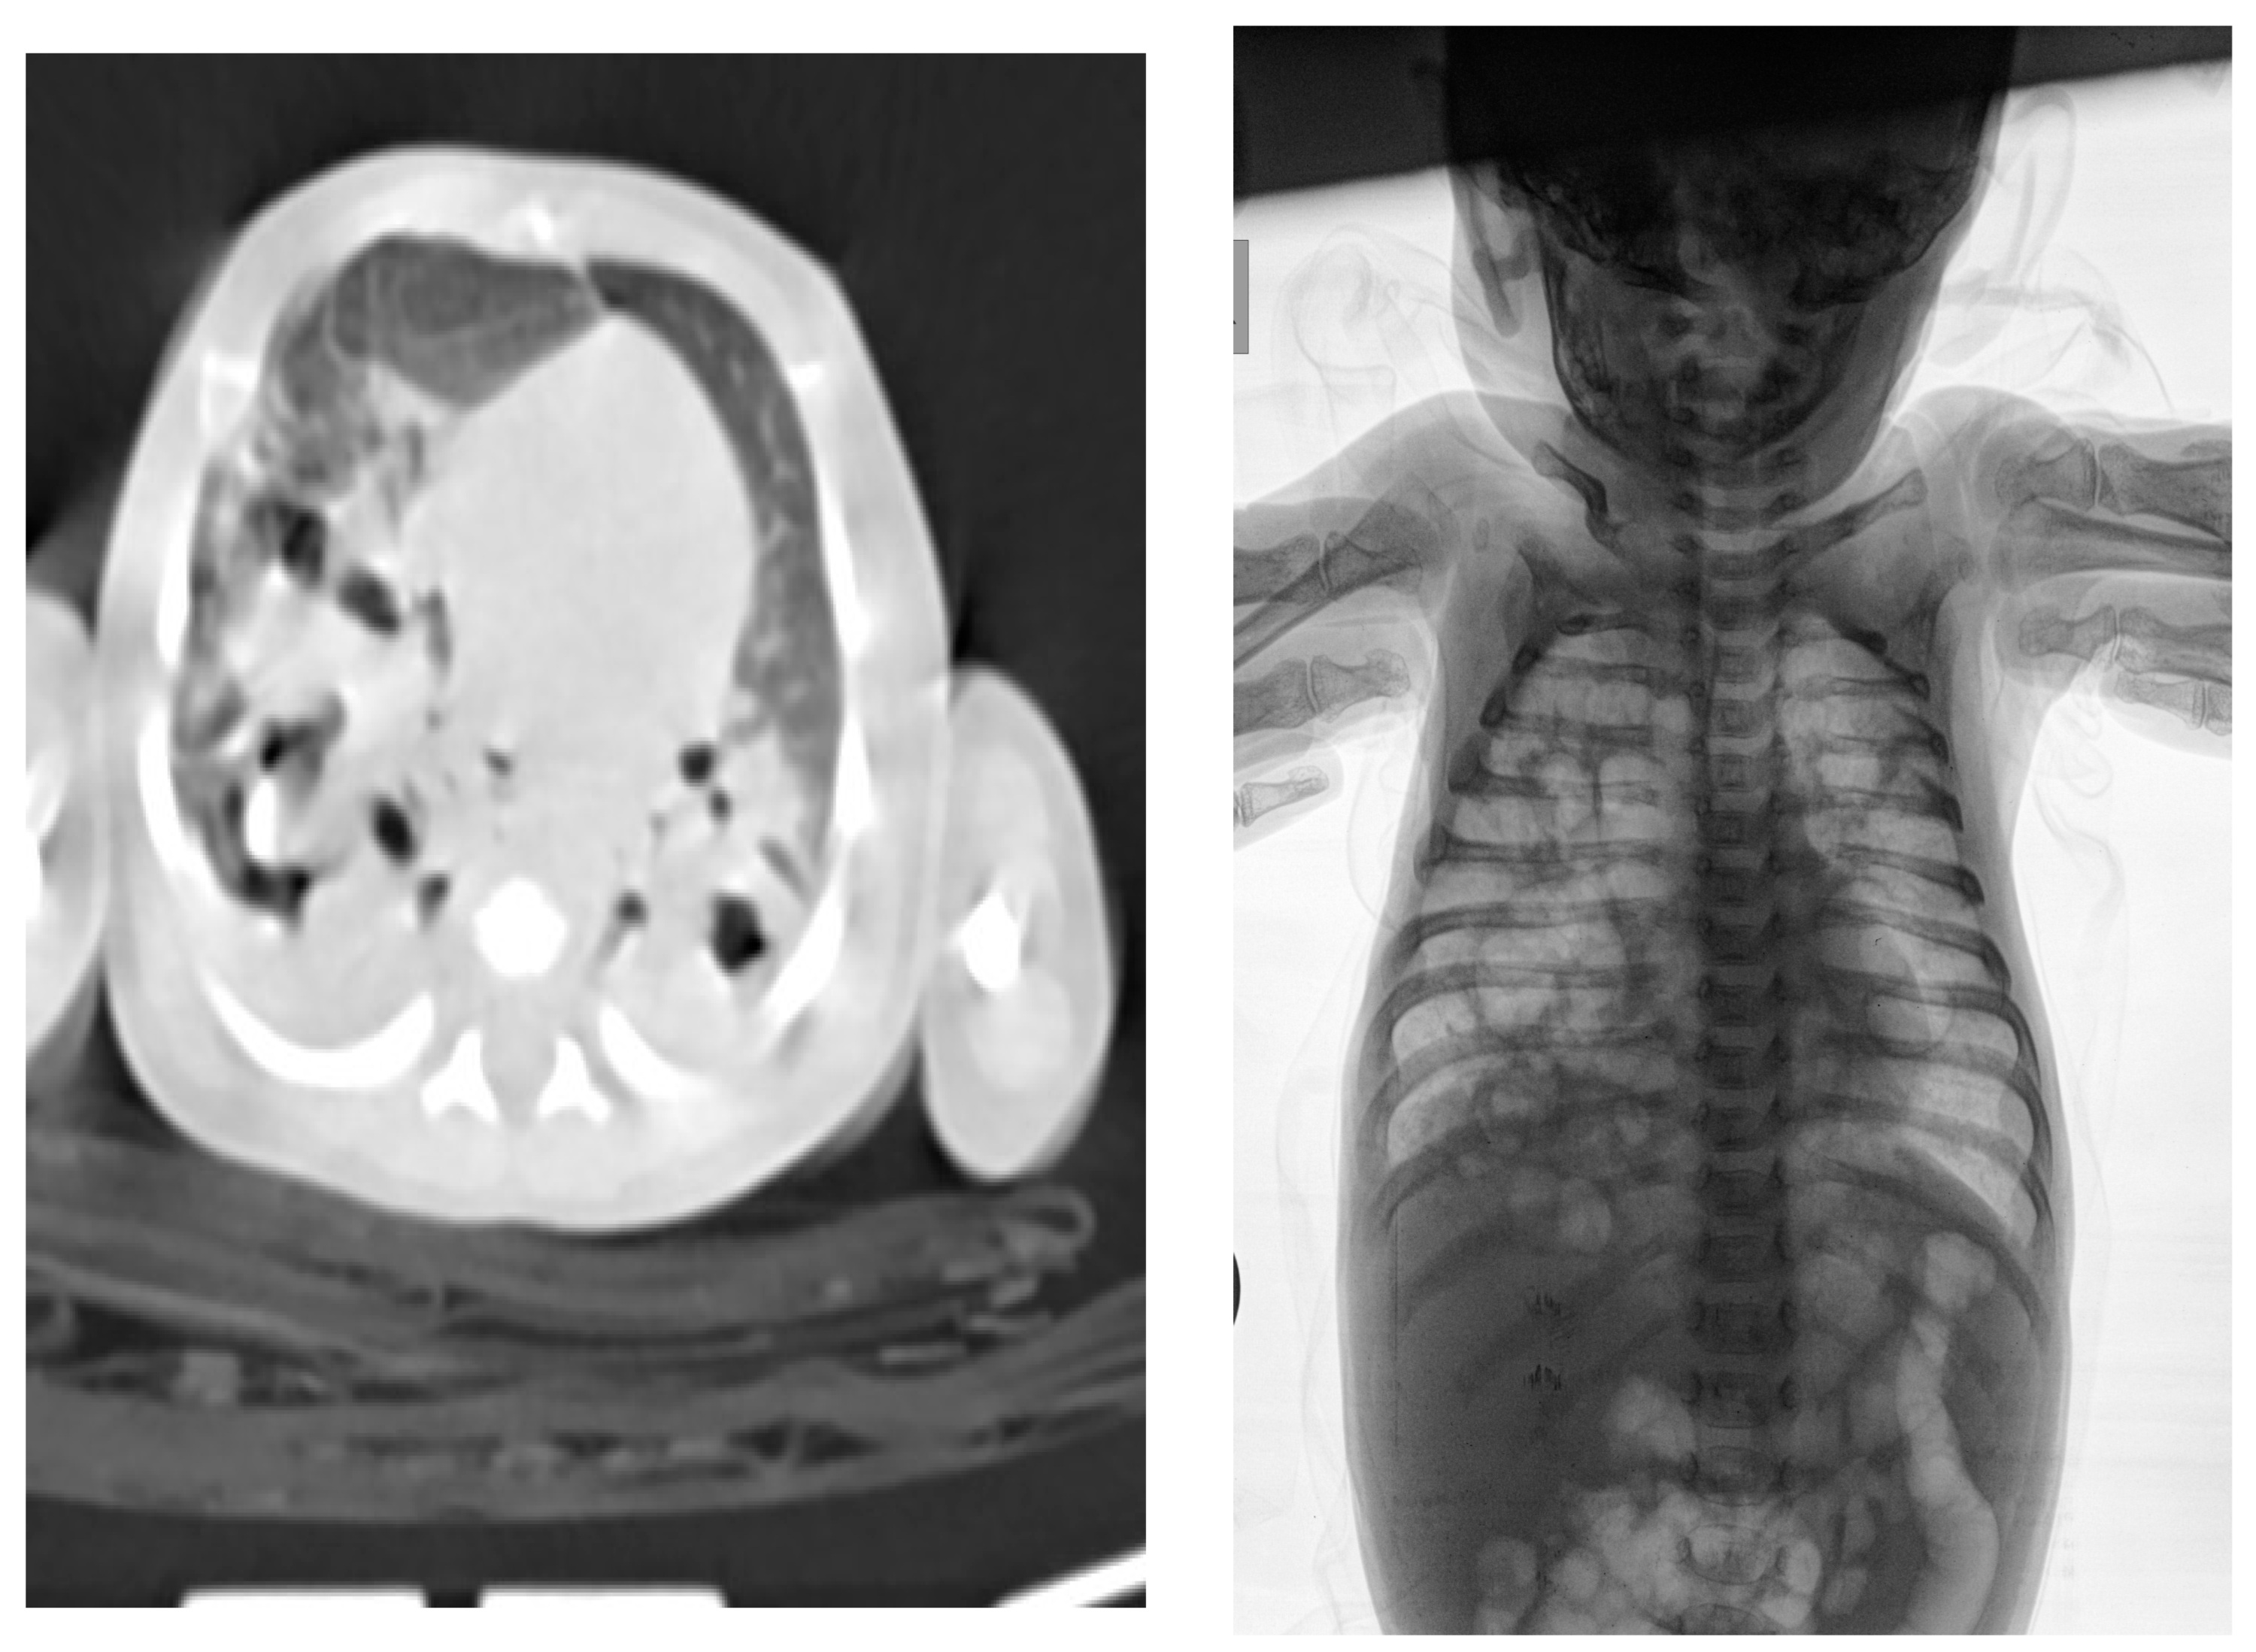

2. Commentary